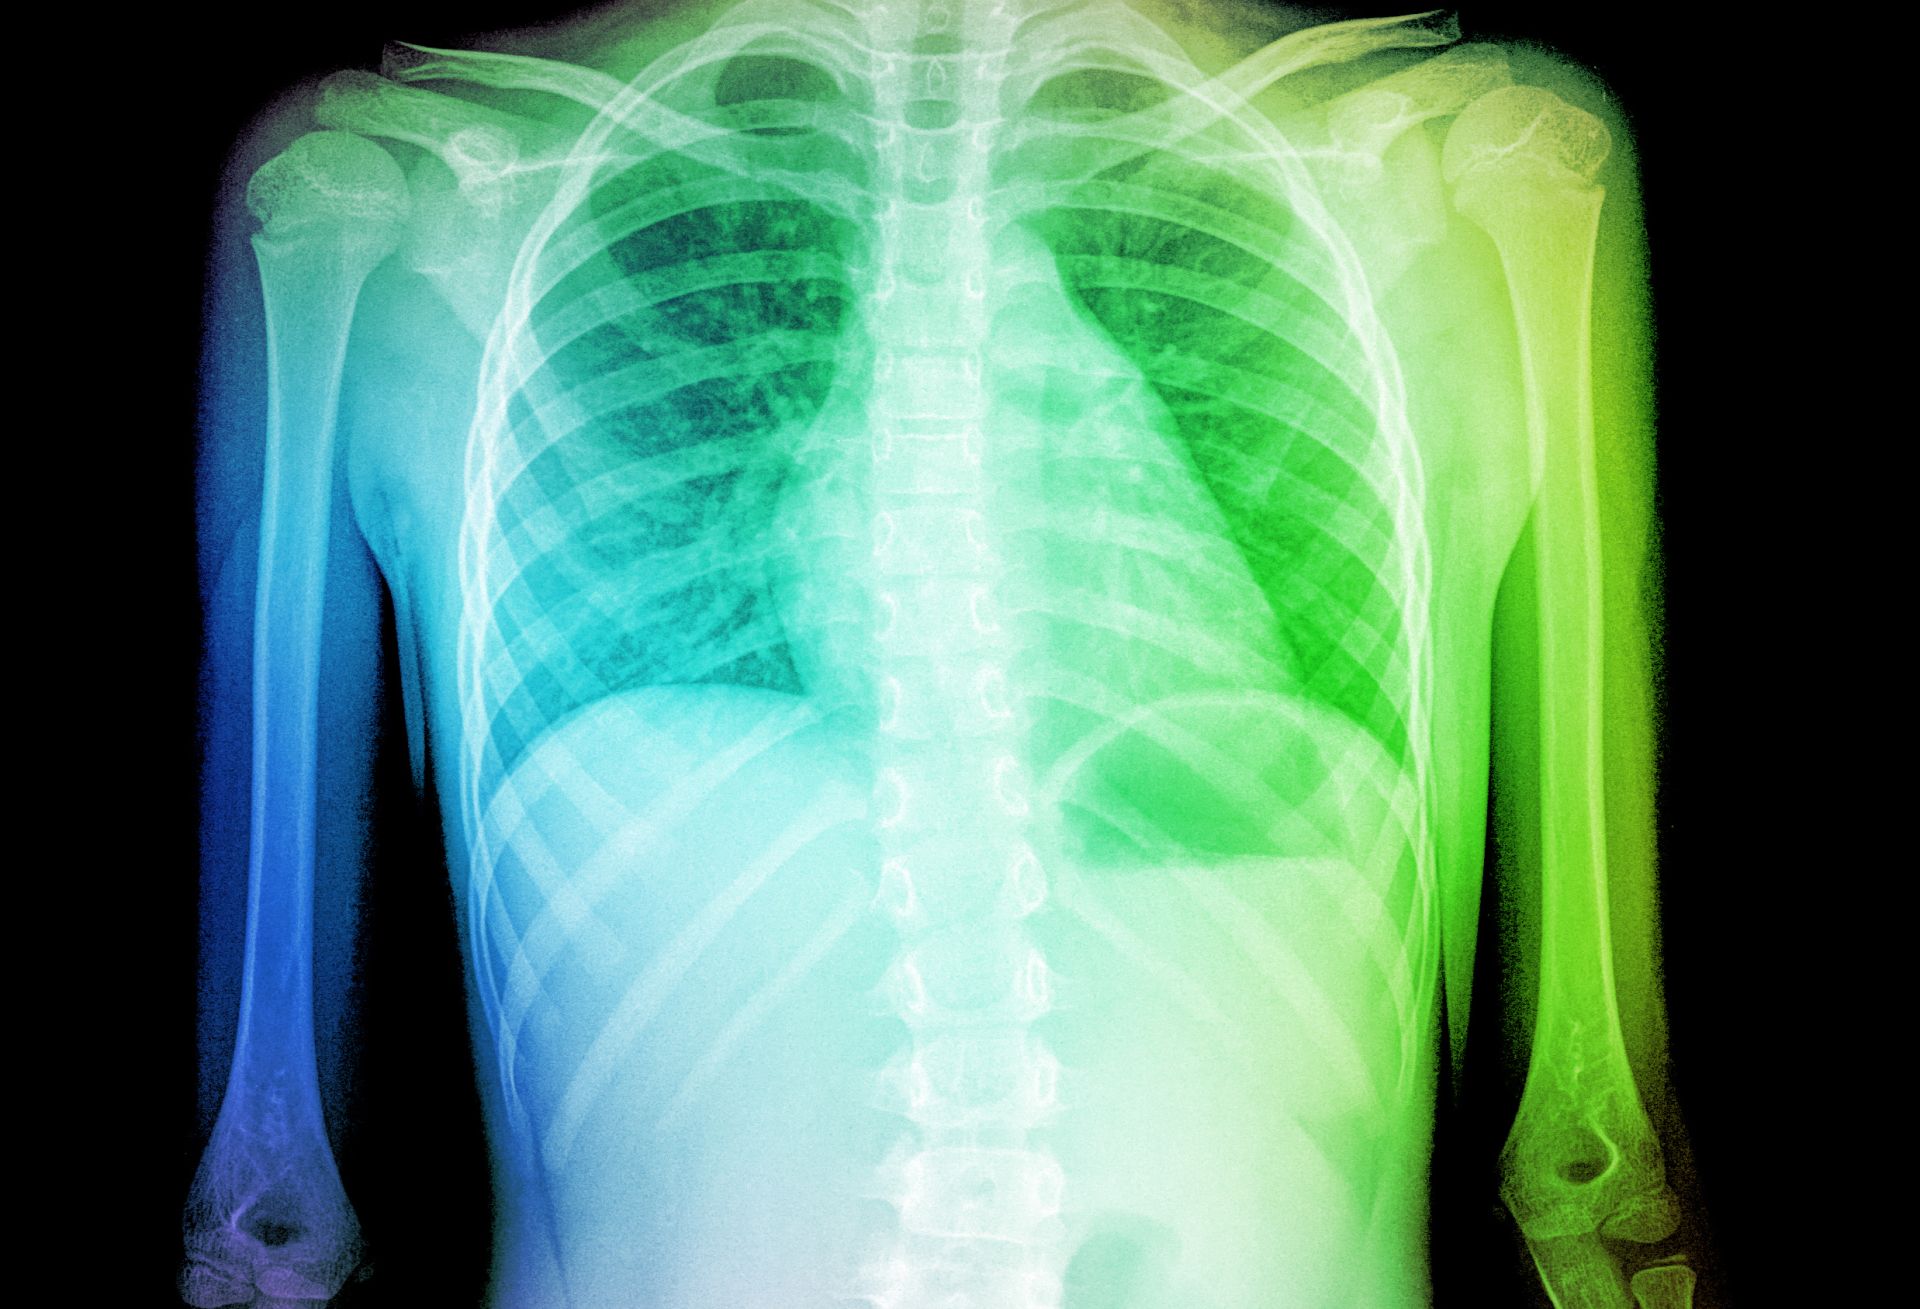

Jos terveydenhoitaja epäilee skolioosia, hän lähettää lapsen/nuoren koululääkärille. Lääkäri tutkii potilaan ja lähettää tämän tarvittaessa edelleen erikoissairaanhoitoon lastenortopedille, joka selvittää, millaisesta skolioosista on kyse. Lopullinen diagnoosi edellyttää röntgenkuvausta.

Korsettihoidon etenemistä seurataan suunnilleen 6–9 kuukauden välein. Osan tutkimuksista lääkäri tekee scolimetriä käyttämällä ja osan röntgenkuvia tutkimalla.